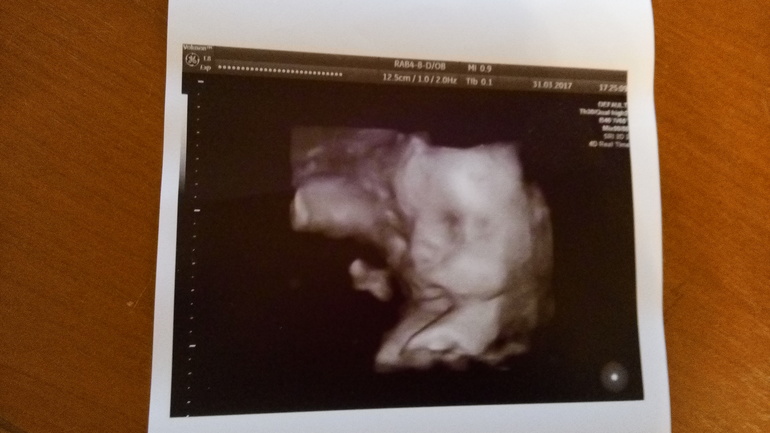

Наши 28.5 недель)

Сегодня съездили на УЗИ. Перед УЗИ съела сладкий пирожок и выпила капучино. Думала, что мелкий расшевелить счет от сладкого. Да не тут то было. Далее по кат.Наш малыш любитель поспать во время УЗИ) Вот и сегодня он в очередной раз доказал, что УЗИ нисколько не причиняет ему неудобств. Как ни пыталась его врач расшевелить, он сладко спал с полным желудком. Как настоящий мужчина - поел и на боковую. И ничто его не могло потревожить) Свернулся клубочком - коленками упирался в лоб. Так что четких фото в 3д, как я надеялась, не получилось. Но все же мы разглядели пухленькие щечки и не менее пухлые губки) . Весит уже 1500 кг примерно. Все соответствует сроку. А вот ноги и руки, как и в 16 недель , опережают по длине на неделю, полторы. Баскетболист там у нас похоже растет))) Руки на 30 недель, а ноги аж на 30.5! Похоже , опять вылитый муж.) Дочь у нас вылитый папа и лицом фигура ( ноги от ушей)))) Сынуля , видимо тоже))) Тонус мой чудесным образом исчез и миома тоже. Как ни старались, не нашли). Пока сидим на попе. Надеюсь, успеем перевернуться в головное.